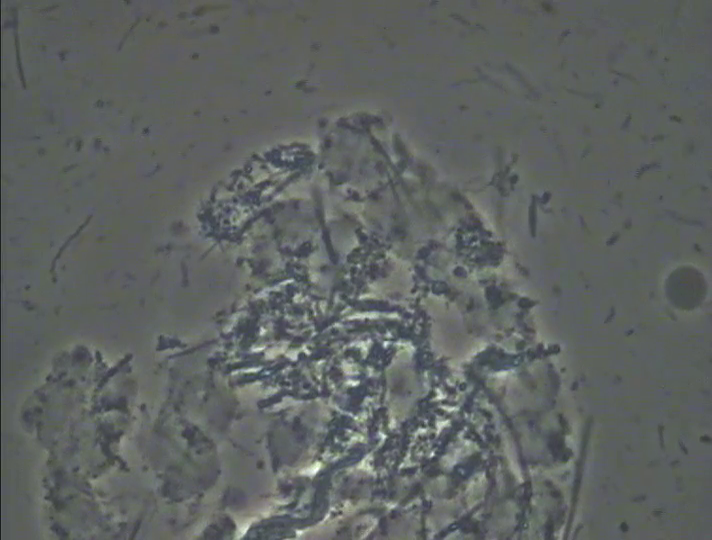

そこで、Nさんに説明をしてカウンセリング(歯周病のPCR検査や口臭検査、マイクロスコープを使用した口腔内の細かい所までの診療)に変更させていただきました。